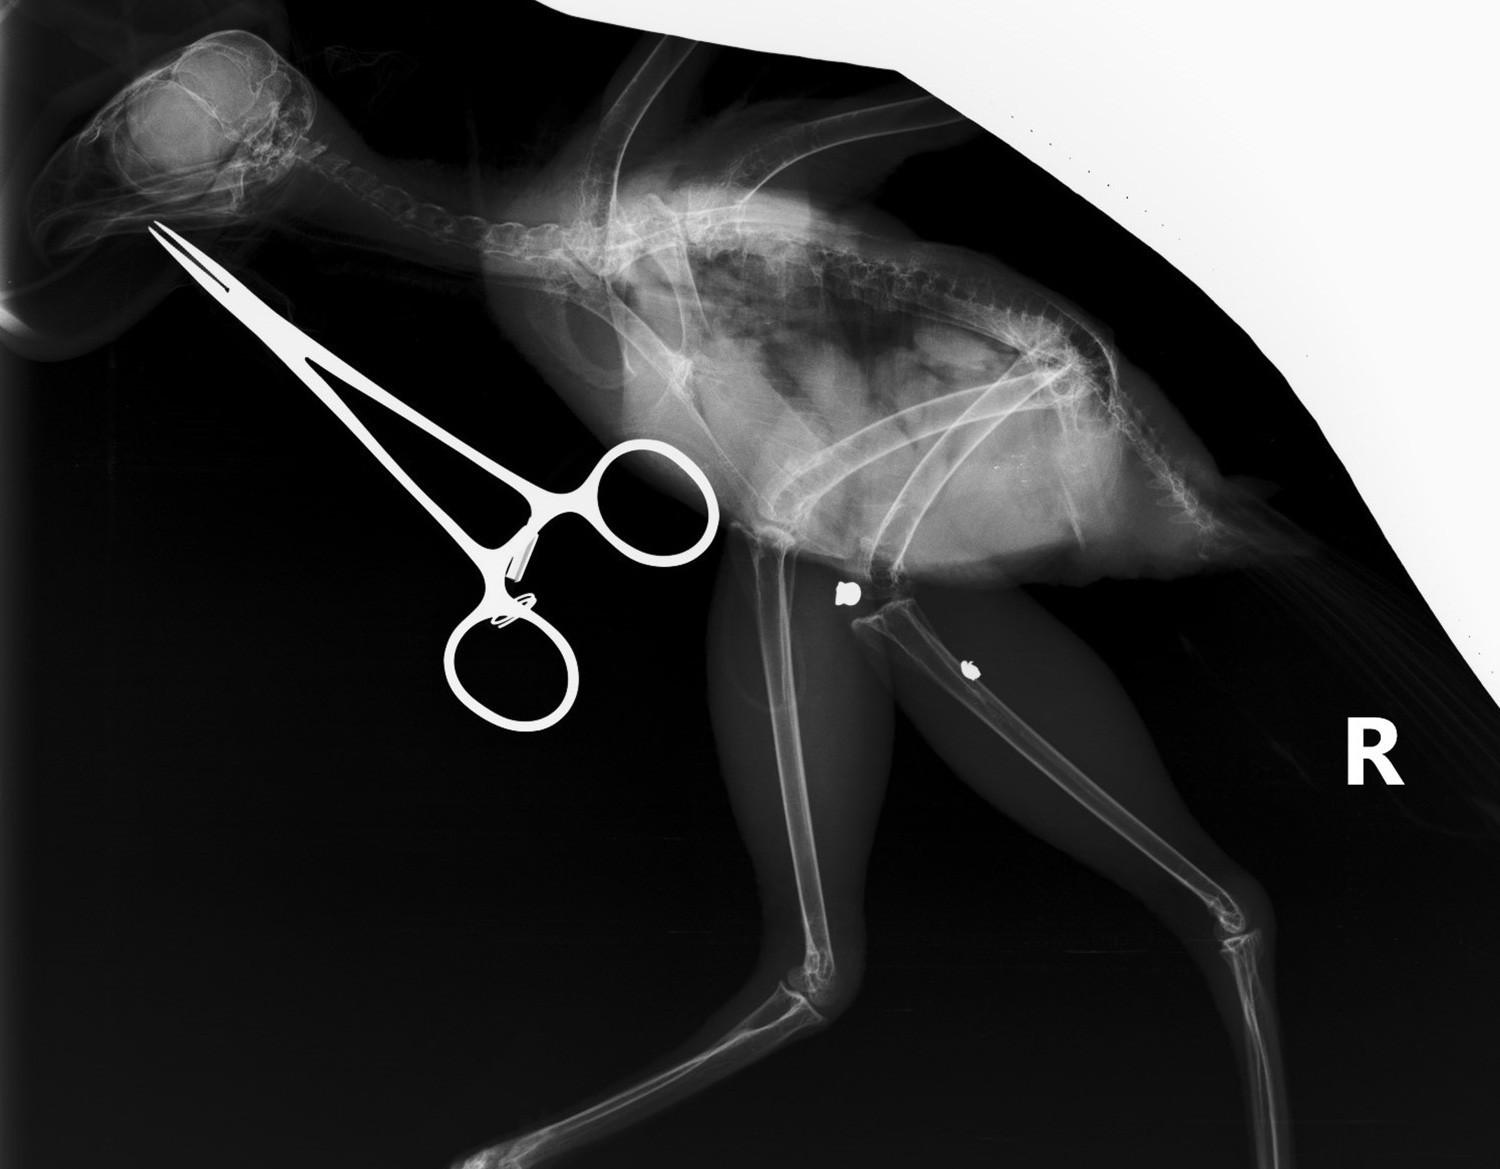

該隻鳳頭鷹最近因翅膀受傷,被送到園方的野生動物拯救中心。在進行X光檢查時,團隊發現牠的腿部隱藏著另一處傷勢,牠的右腿曾被氣槍鋼彈擊中。衝擊力不但打斷了右腓骨,還使鋼彈碎裂,一塊較大的碎片移動到去膝關節,另一塊較小的碎片則嵌入脛跗骨中。園方分析這個傷勢已經有一段時間,令人意外是該隻鳳頭鷹仍能正常使用牠的腳和爪。

園方通過一個小的皮膚切口,輕鬆取出較大的鋼彈碎片;至於較小且深的碎片,則因移除的風險大於好處,而被保留下來。經過幾天的傷口處理後,資深獸醫為鳳頭鷹受傷的翅膀進行了修復手術。鳳頭鷹目前康復進度良好,並正在進行康復訓練,為重返大自然做好準備。